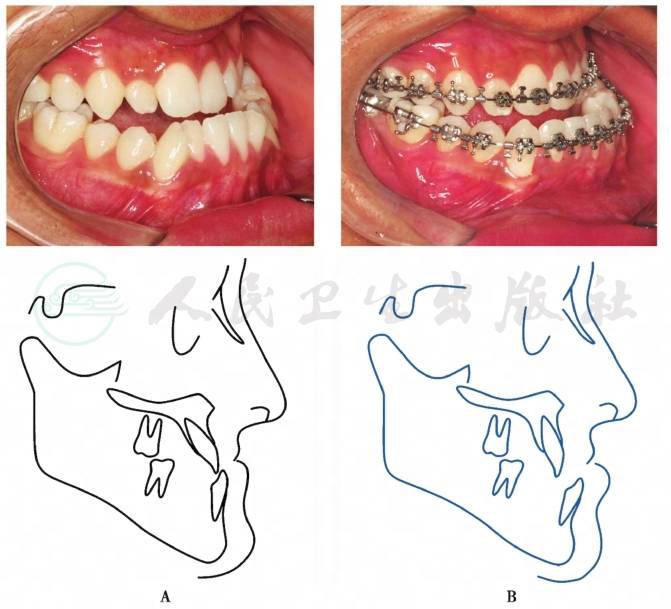

1.排齐牙列,去除牙代偿性倾斜与干扰,释放限制颌骨移动的因素(图8)。

图8骨性Ⅲ类错𬌗的去除牙代偿

A.去牙代偿前 B.去牙代偿后

引自:口腔颌面外科学(第8版).第1版.ISBN:978-7-117-29388-4.主编:

相反,如果不进行术前正畸治疗,术中颌骨的移动阻力较大,移动量受到限制,最重要的是术后遗留的牙畸形仍不美观,即使术后再行补救性正畸治疗,其治疗难度和时间相应增加,而且治疗效果常不满意。因此,对绝大多数颌骨发育异常导致的牙颌面畸形,急功近利地采用单纯的外科手术难以获取功能和形态都满意的治疗效果。